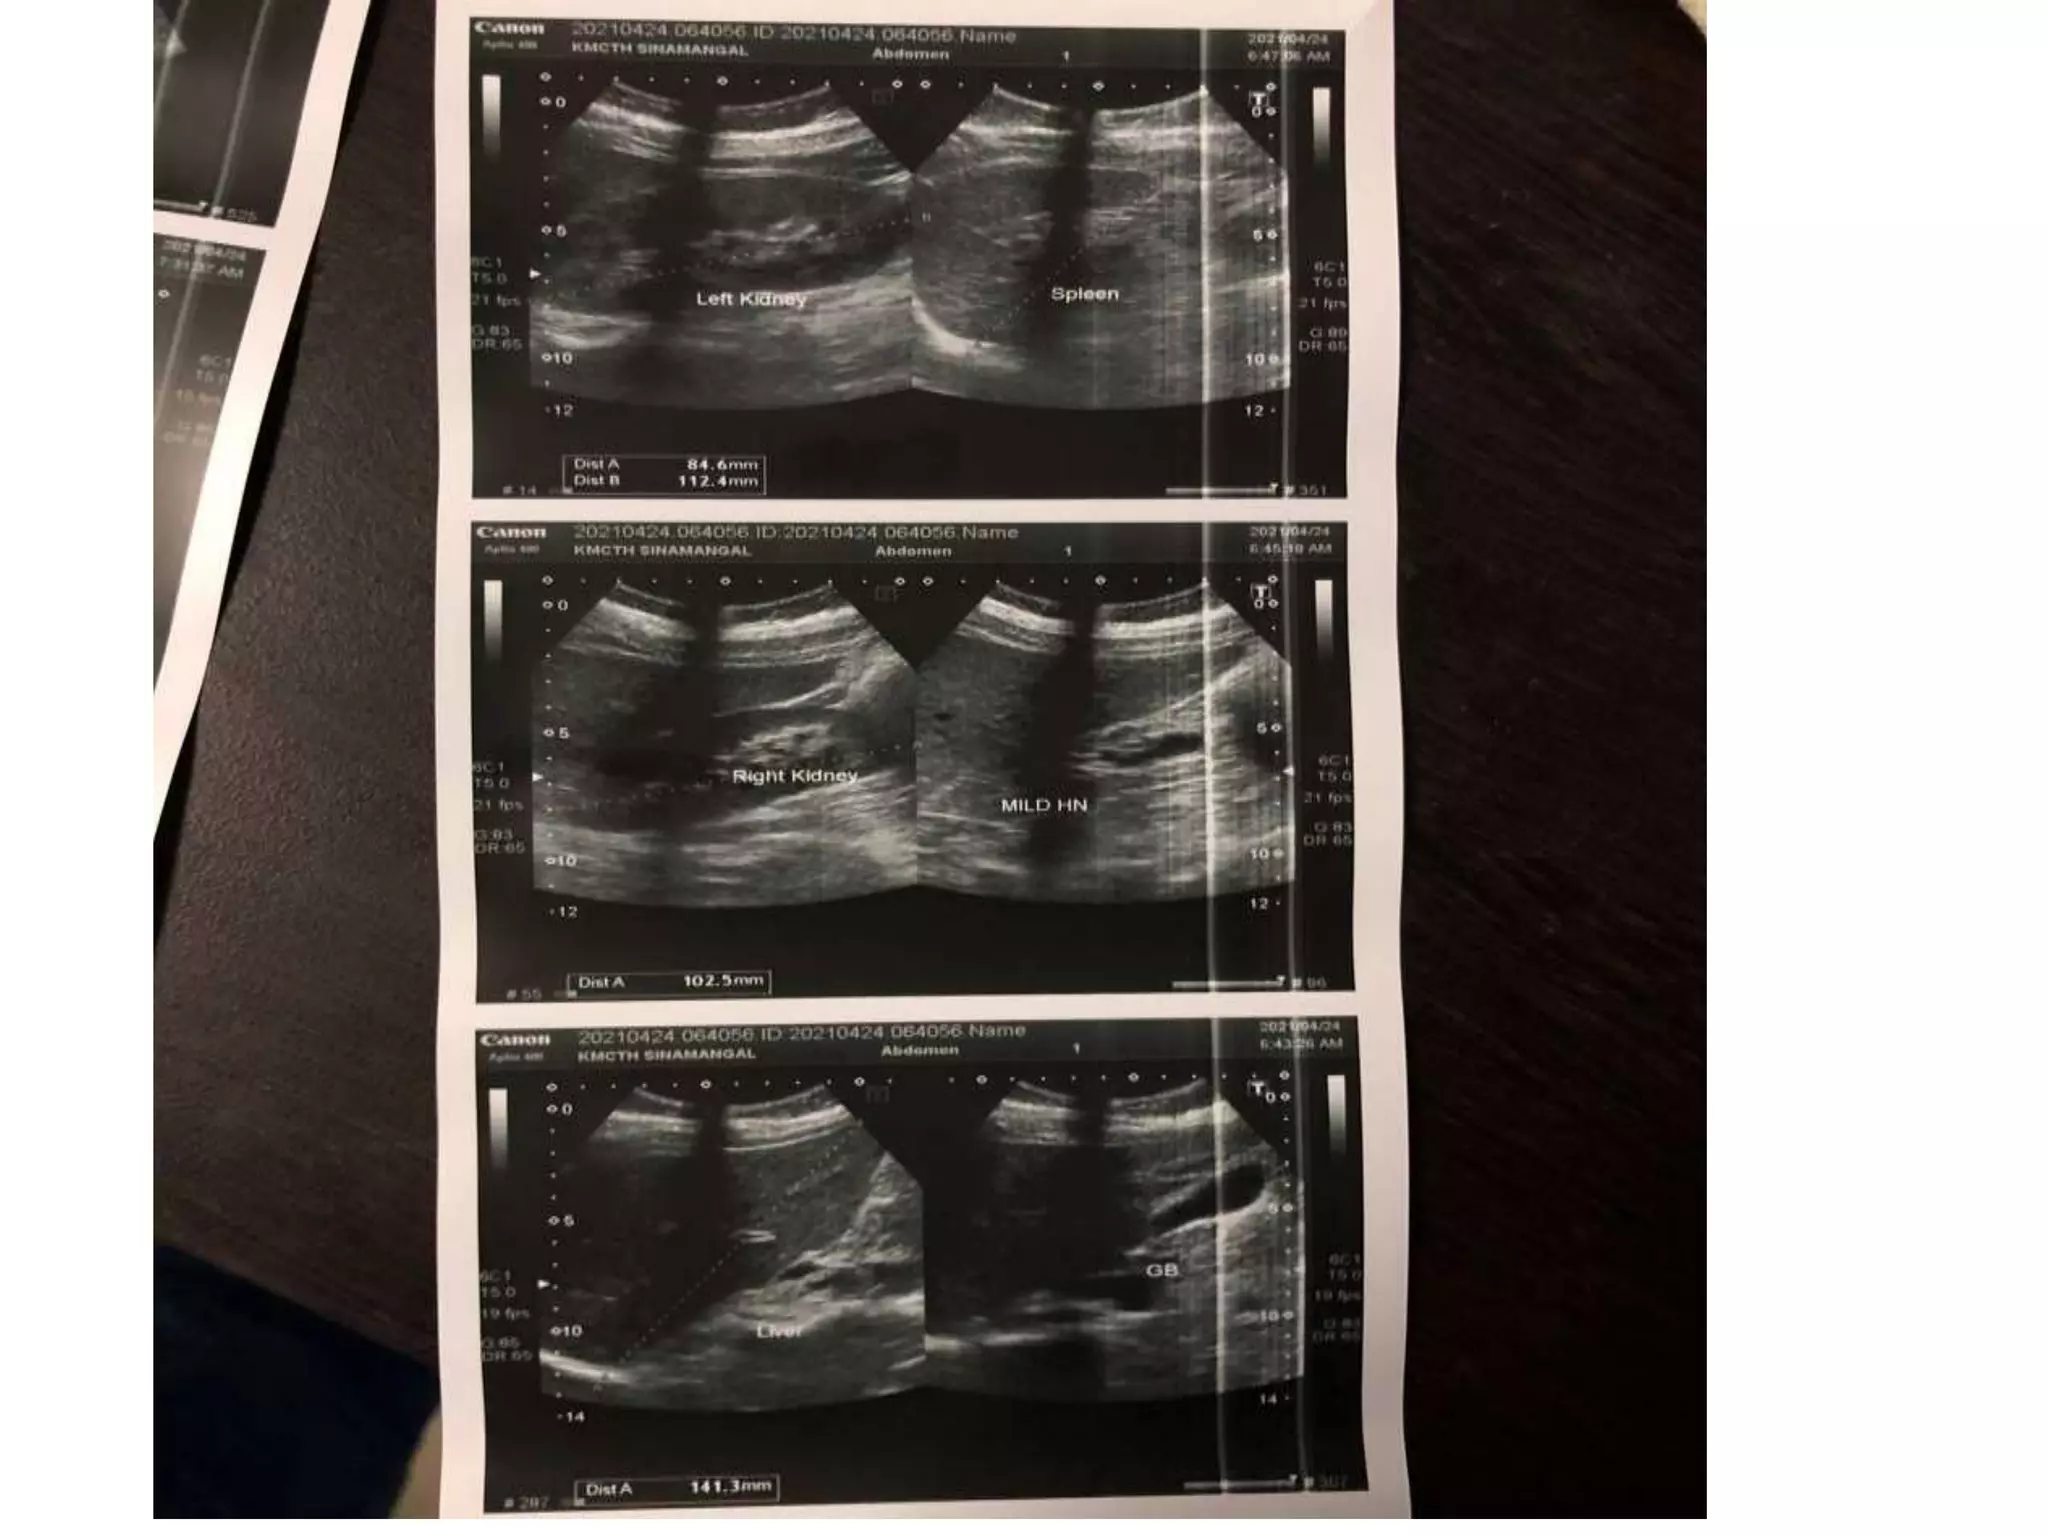

A 35-year-old woman presented with severe lower abdominal pain and difficulty urinating. An ultrasound revealed she had two separate uteruses with separate cervical canals but a normal vaginal canal, consistent with a bicornate bicollis uterus. This type of uterus is a müllerian duct anomaly that can result from interrupted development of the müllerian ducts in utero. Müllerian duct anomalies are associated with renal, vertebral, and cardiac anomalies as well as infertility and menstrual disturbances.